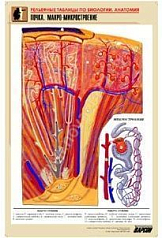

13. Долька печени. Макро-микростроение;

17. Почка. Макро-микростроение;